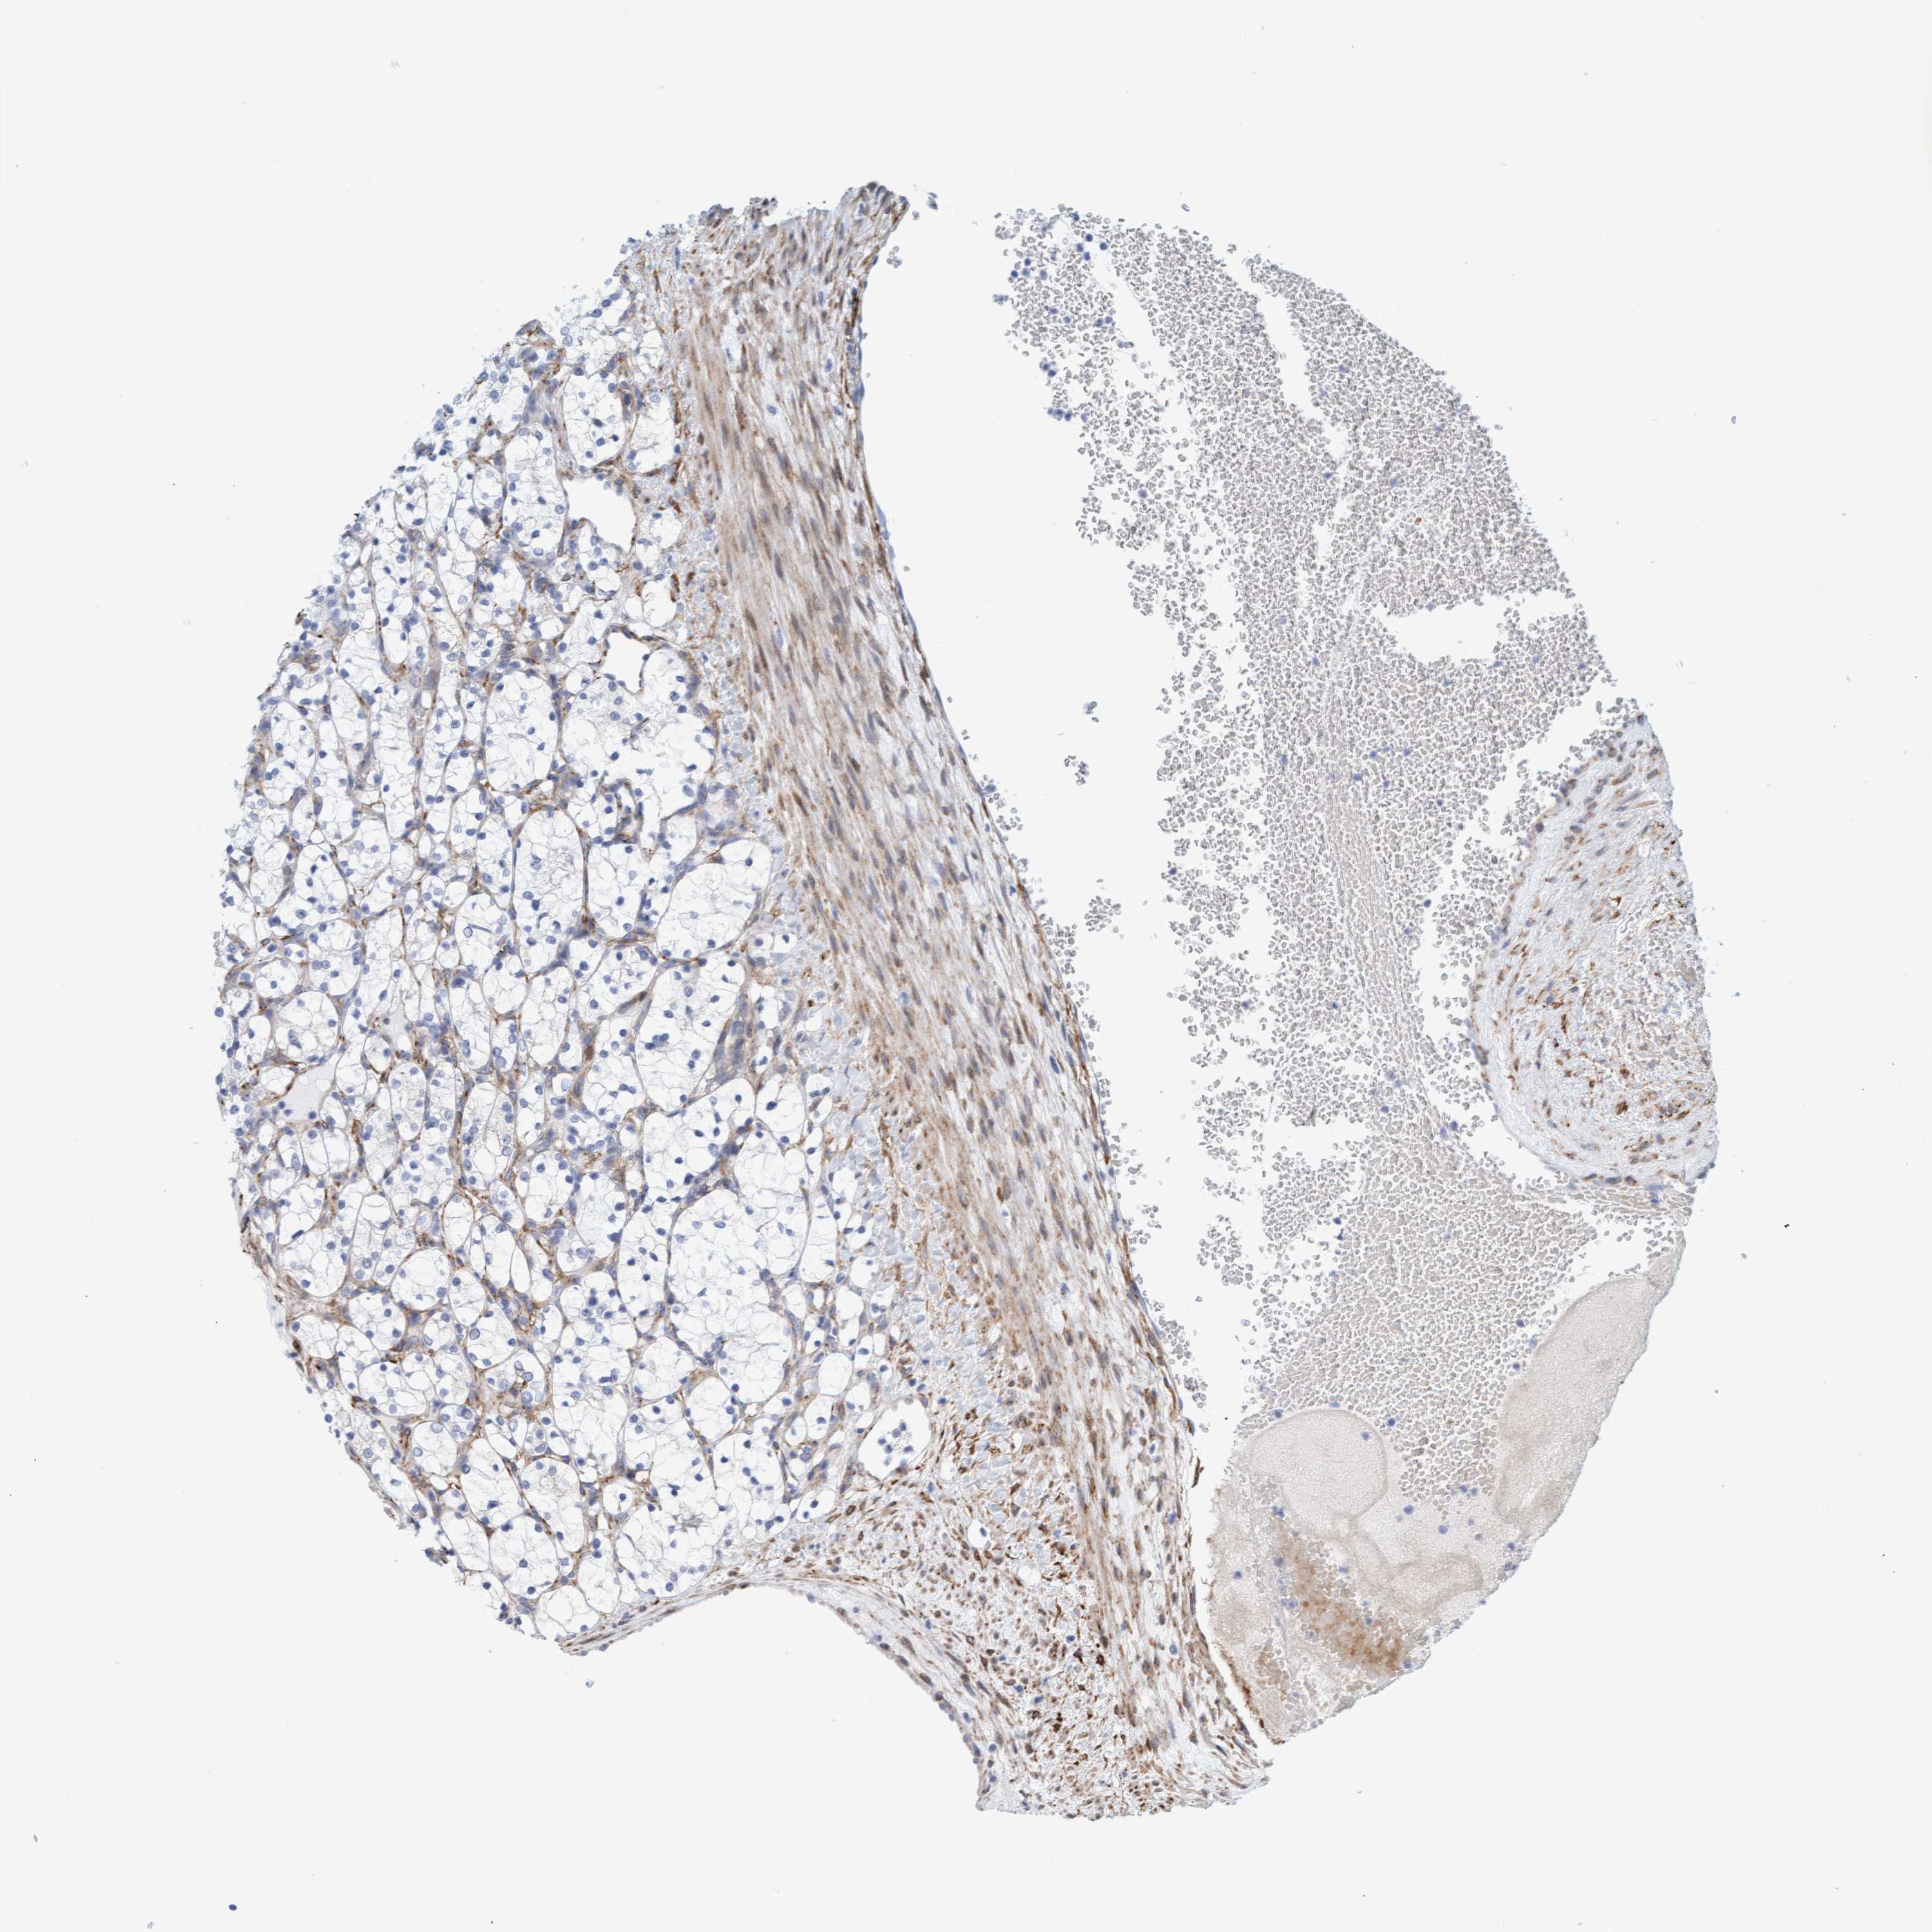

CANCER RENAL CANCER Show tissue menu

KICH TCGA KIRC TCGA KIRC VALIDATION KIRP TCGA PROTEIN RCC CPTAC PROTEIN EXPRESSION